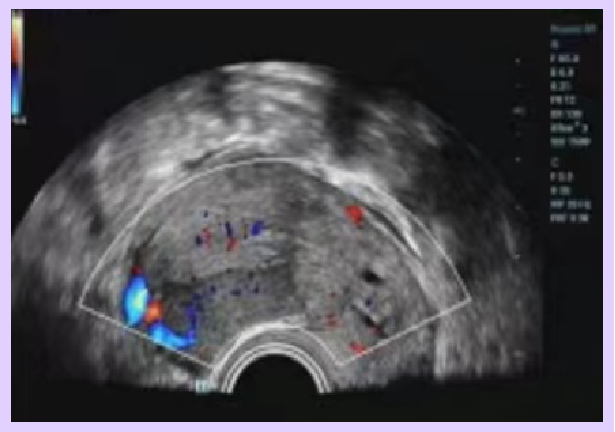

| 5 weeks | 41,759 | 15.06 | Gestational sac: 24×18×10 mm, yolk sac: 3.3 mm, no fetal heartbeat or embryo visible |

| 6 weeks | – | – | Gestational sac: 30×22×19 mm, yolk sac: 3.1 mm, fetal heartbeat and embryo (5×3 mm) visible |

▲ Ms. A’s ultrasound image